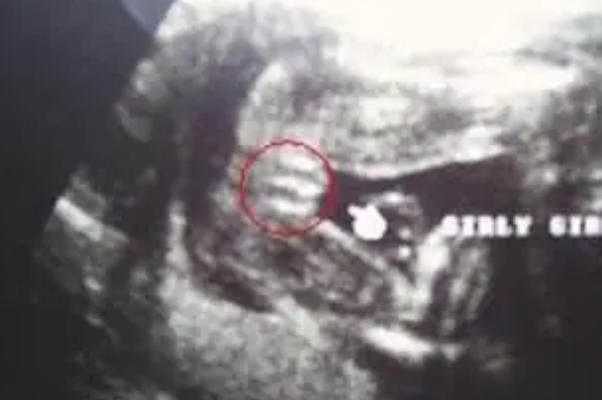

咱们先来说说这个“三条线”到底是什么东西。在孕中晚期做B超检查时,如果胎儿的体位合适,超声医生会观察胎儿的外生殖器。对于女性胎儿来说,因为大阴唇和小阴唇的结构,在超声图像上会呈现出三条平行的、浅浅的线状回声。简单来说,这就是女孩外阴的一个典型影像特征,有点像一个小小的“三明治”或者“贝壳”的样子。

所以,严格来讲,如果在B超报告上清晰地看到了“三条线”,这通常意味着你怀的是个“小棉袄”。而很多孕妈听说的“有就是女孩,没有就是男孩”,这个说法大体上是对的。但问题就出在,很多人把因果关系搞反了,还在那儿追问“什么样的三条线是男孩”,这就像一个劲儿地问“什么样的苹果是橘子”一样,本身就是一个伪命题。男孩的特征不是看三条线,而是看另一个标志性的东西,咱们下面再说。

所以,回到咱们的核心问题“什么样的三条线是男孩”,标准答案就是:不存在。男孩不看线,女孩才看线。如果你在B超单上真的看到了三条线,那恰恰说明是女孩;如果你看不到三条线,而是看到一个向上翘起的凸起结构,那多半就是男孩。当然,这需要专业的超声医生在合适的孕周、合适的体位下才能准确判断。